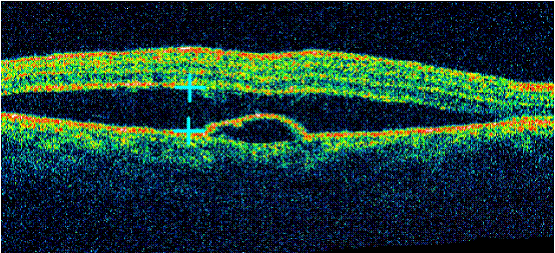

Bệnh  hắc võng mạc trung tâm thanh dịch có bong biểu mô sắc tố

Bệnh võng mạc trẻ đẻ non( ROP), bệnh võng mạc đái tháo đường, hai bệnh lý gây mù lòa hàng đầu trên trẻ em và người già nhờ có OCT  đã có thể chẩn đoán được hình thái, nguyên nhân, lên phương án điều trị. Hàng chục năm trước rất nhiều tổn thương đã không được đánh giá đầy đủ  vì các bác sĩ chỉ có trong tay phương pháp chụp mạch hùynh quang. Đối với bệnh hắc võng mạc trung tâm thanh dịch, OCT có thể cho thấy được dịch tích tụ giữa lớp thần kinh cảm thụ và lớp biểu mô sắc tố của võng mạc, đo được kích thước của khối dịch. Ngoài ra, còn có thể xác định vị trí của điểm dò qua vị trí tổn hại hoặc bong lớp biểu mô sắc tố. Trong bệnh lỗ hoàng điểm, OCT xác định có lỗ hoàng điểm, đo được kích thước của lỗ hoàng điểm, có thể thấy được co kéo dịch kính võng mạc gây ra lỗ hoàng điểm và chiều dày võng mạc vùng xung quanh lỗ hoàng điểm...